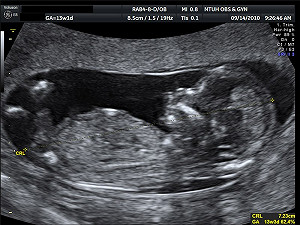

胎兒超音波 未要求掃描四肢 監院促改善